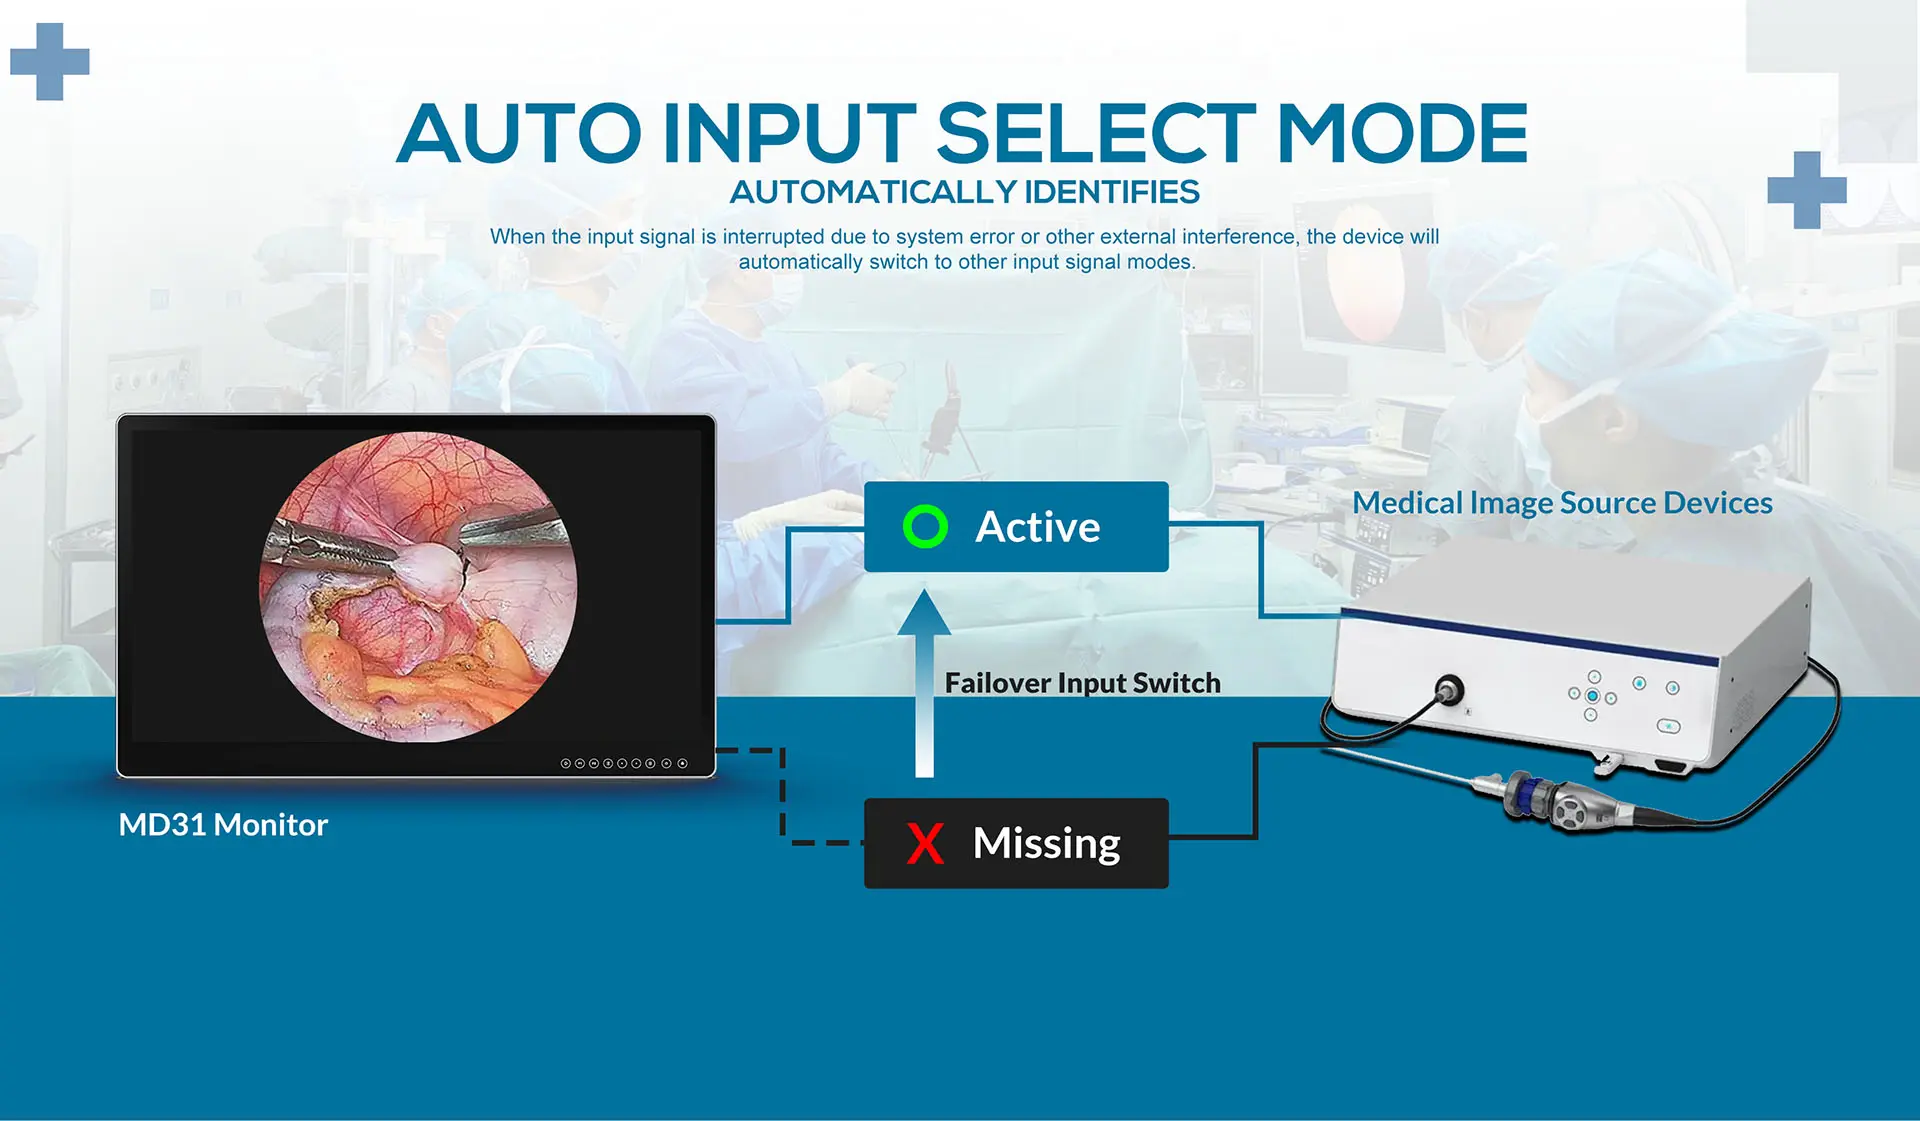

MD31 is a 31.5" 4K surgical monitor for endoscopy and surgery, with accurate color reproduction, clear contrast and vivid video images, providing surgeons and operating staff with real-time, accurate color images. Antibacterial housing and optical bonding technology are easy to clean and disinfect. A variety of video input andoutput interfaces can accommodate video signals from various medical imaging sources to meet the requirements of various applications in the operating room.